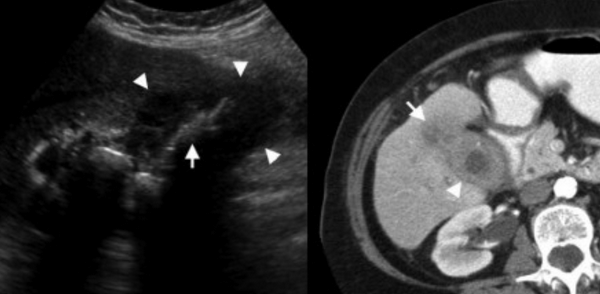

Слева — УЗИ — желчного пузыря у 59 летней женщины с острым холециститом. Субсерозный отек так, как гипоэхогенное утолщение между гиперэхогенными слоями (мышечным и слизистым). Справа — КТ брюшной полости с контрастным усилением. Также визуализируется субсерозный отек так, как наружный слой гиподенсный.

Острый калькулезный холецистит. После контрастного усиления визуализируется растянутый желчный пузырь (белые наконечники) со слегка утолщенной стенкой. Визуализируется камень в шейки желчного пузыря (белая стрелка).

Сверху изображения пациента 62 лет с калькулезным холециститом. На УЗИ визуализируется стенки желчного пузыря растянутые, с субсерозным отеком (указано белыми стрелками) и в просвете желчного пузыря камень и взвесь. На КТ визуализируется переход воспалительного процесса с желчного пузыря на соседние ткани (перихолецистит).